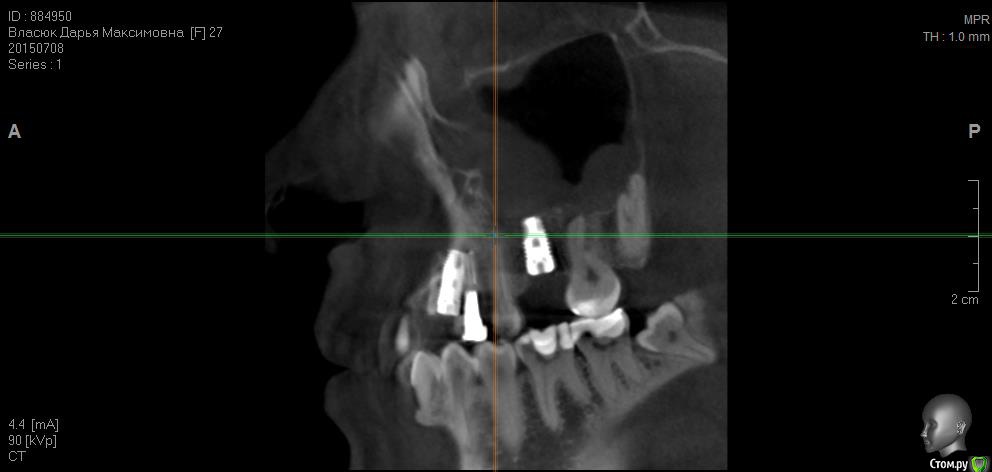

fifa888.dexo Опубликовано 22 июля, 2015 Автор Поделиться Опубликовано 22 июля, 2015 а это все что я могла придумать с кт Ссылка на комментарий

diesel87 Опубликовано 22 июля, 2015 Поделиться Опубликовано 22 июля, 2015 http://fs2.directupload.net/images/150723/9sv48h7l.jpg http://fs1.directupload.net/images/150723/9nsd29hm.jpg http://fs2.directupload.net/images/150723/q4s456ou.jpg http://fs2.directupload.net/images/150723/9x7h27mc.jpg По КТ:1.возможно имплант в области клыка в апексе (самой верхней части) контактирует с четверкой (не ясно из-за того что имплант фонит), если четверка не реагирует, то пока наблюдать, делать прицельные снимки раз в 3/6/9/12 месяцев.2. Не докрученный формирователь, особо не страшно, но в щель может врасти десна, будет запах, локальное воспаление в области шейки импланта, так что лучше его докрутить или если он упирается в соседние зубы, поменять на узкий и докрутить.3. Имплант что в синусе, по снимку он практически весь в кости, а "воспаление" могло быть там и ранее, есть снимки до операции?? Ссылка на комментарий